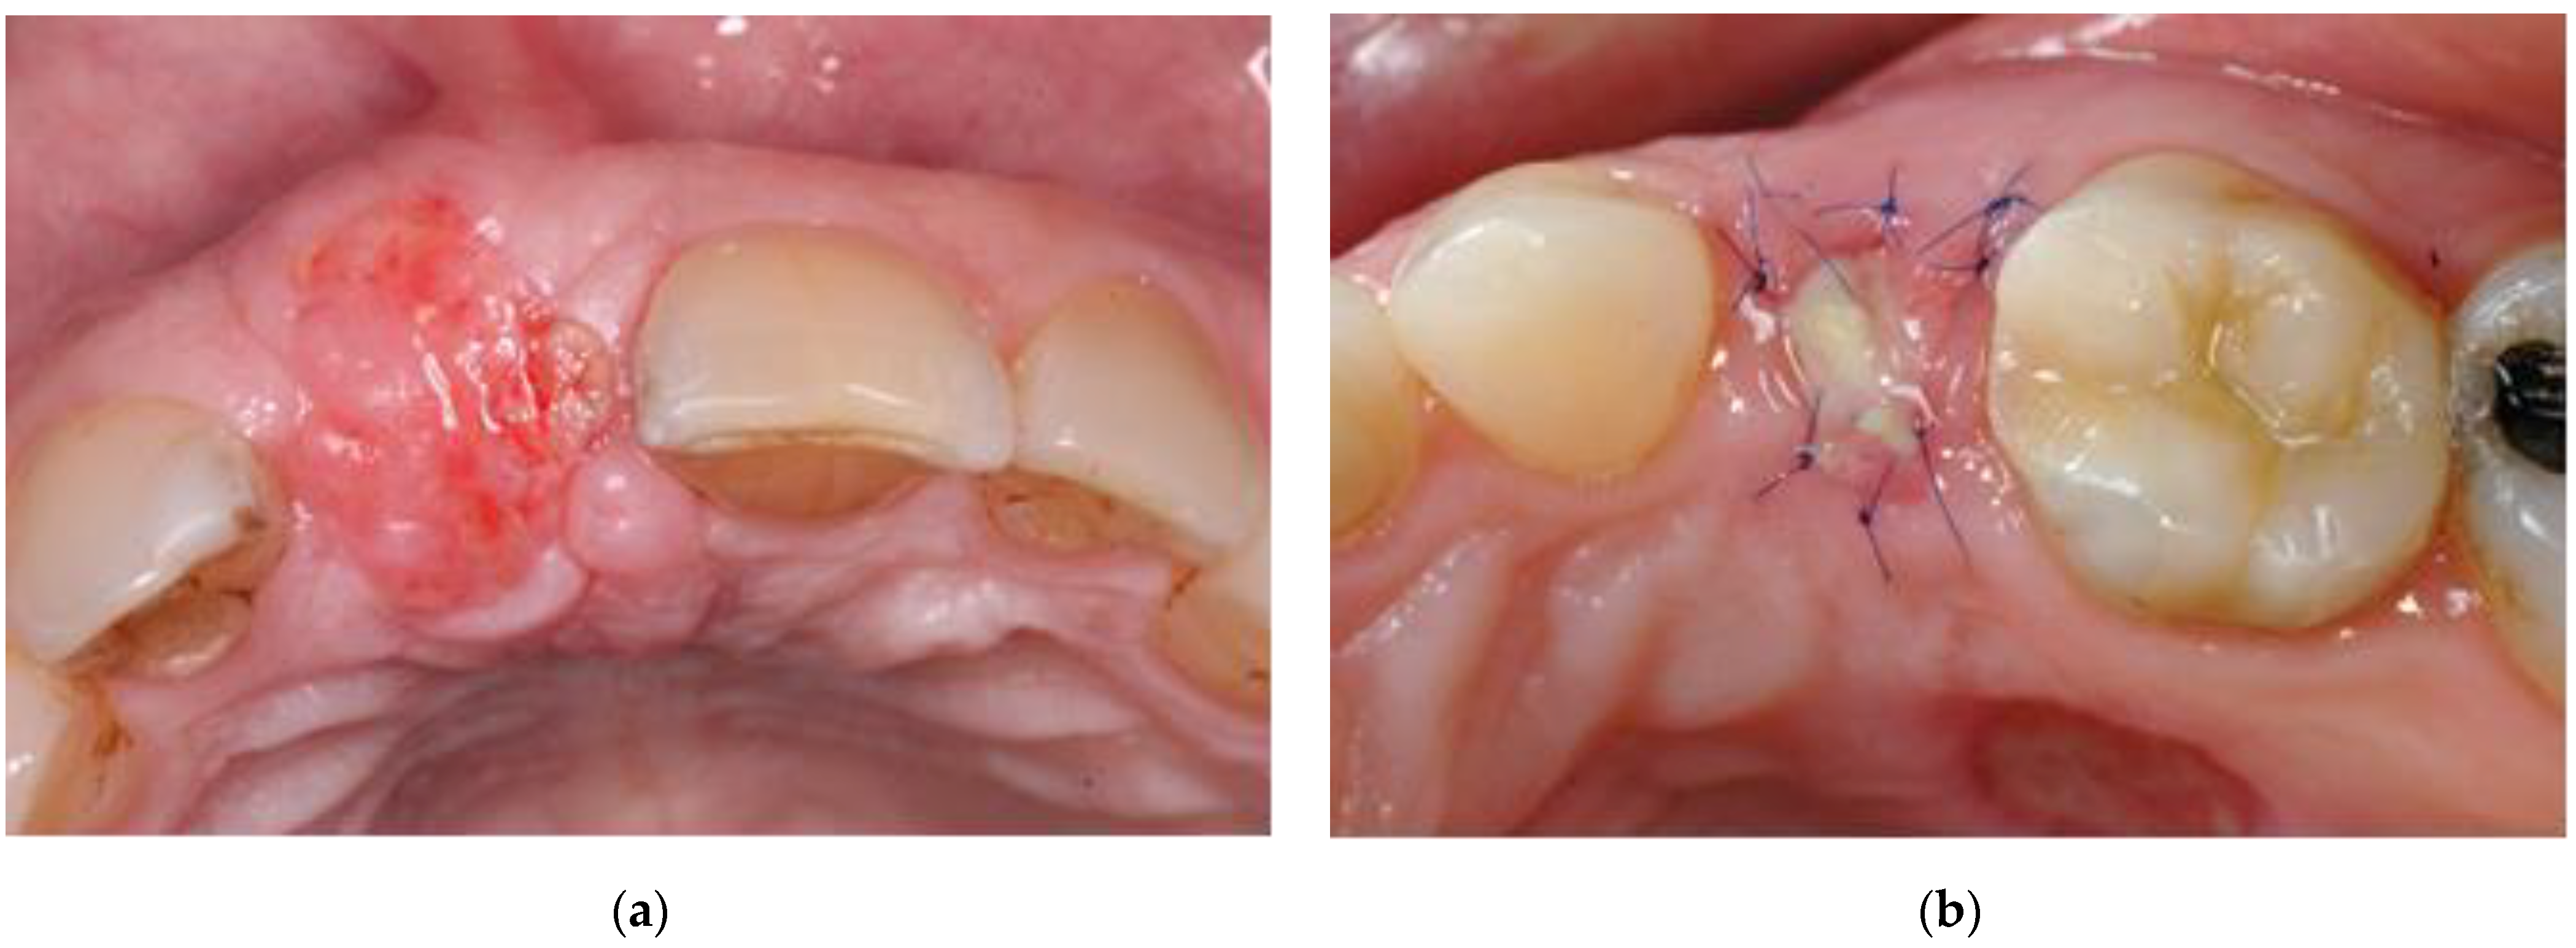

- Vital: reddish tissue color indicating the graft has integration of blood supply (Figure 2a).

- Partially vital: part of the graft presented signs of vitality (as mentioned above) and another part showed signs of necrosis, i.e., amorphous white material (Figure 2b).